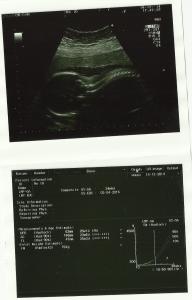

Sinds gisteren mag ik elke dag aan de monitor, zodat van nabij kan opgevolgd worden hoe het met jou gaat! Ik wou vandaag toch nog even voor een bewijs zorgen van het feit dat je zoveel beweegt in mama’s buik. Op de uitprint van de monitor zie je drie lijntjes:

– links: jouw hartslag,

– in het midden: jouw bewegingen (een blokje betekent aaneensluitende bewegingen),

– rechts: weeënactiviteit.

De uitprint van vandaag heeft dus terug aan dat je echt aan het dansen bent in mama’s buik! Je bent zelfs soms zo actief dat mama denkt dat ze harde buiken heeft terwijl jij eigenlijk gewoon aan het bewegen bent.